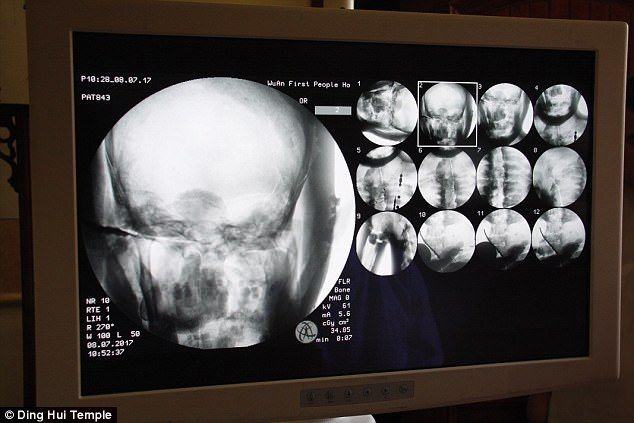

研究學者用X光還有CT掃描檢驗這座高僧坐像,有了驚人的發現:他不但保有完整的骨頭,竟然連大腦都還在,武永慶醫生在受訪時表示:“我們在掃描後發現,他的骨頭跟一般人的一樣完整。”

“上額、上面的牙齒、肋骨、脊椎骨、連關節全部都在,真的是很令人驚奇的情況。”